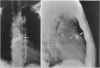

A patient with a functioning intrapericardial paraganglioma (pheochromocytoma) that was located at the root of the aorta overlying the right coronary artery and adherent to the right ventricular wall is reported. The tumour was successfully removed under total cardiopulmonary bypass without inducing cardiac arrest.